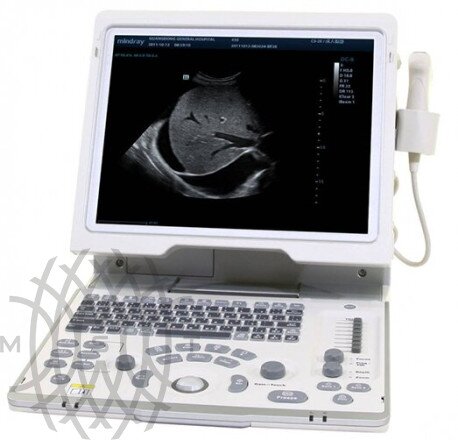

Портативный ультразвуковой аппарат Mindray DP-50

Характеристики портативный ультразвуковой аппарат Mindray DP-50

- Широкоугольный 15-дюймовый ЖК-монитор высокого разрешения с изменяемым углом наклона для лучшего обзора

Mindray DP-50 - цифровая черно-белая ультразвуковая система портативного типа, оснащенная жидкокристаллическим широкоугольным монитором с диагональю 15 дюймов и возможностью изменения наклона для улучшения обзора и удобства врача. УЗИ сканер может работать от аккумулятора, а также от сети. Отличаясь компактными габаритами и имея сравнительно небольшой вес (всего 7,5 кг), легко размещается в помещениях с ограниченным пространством.